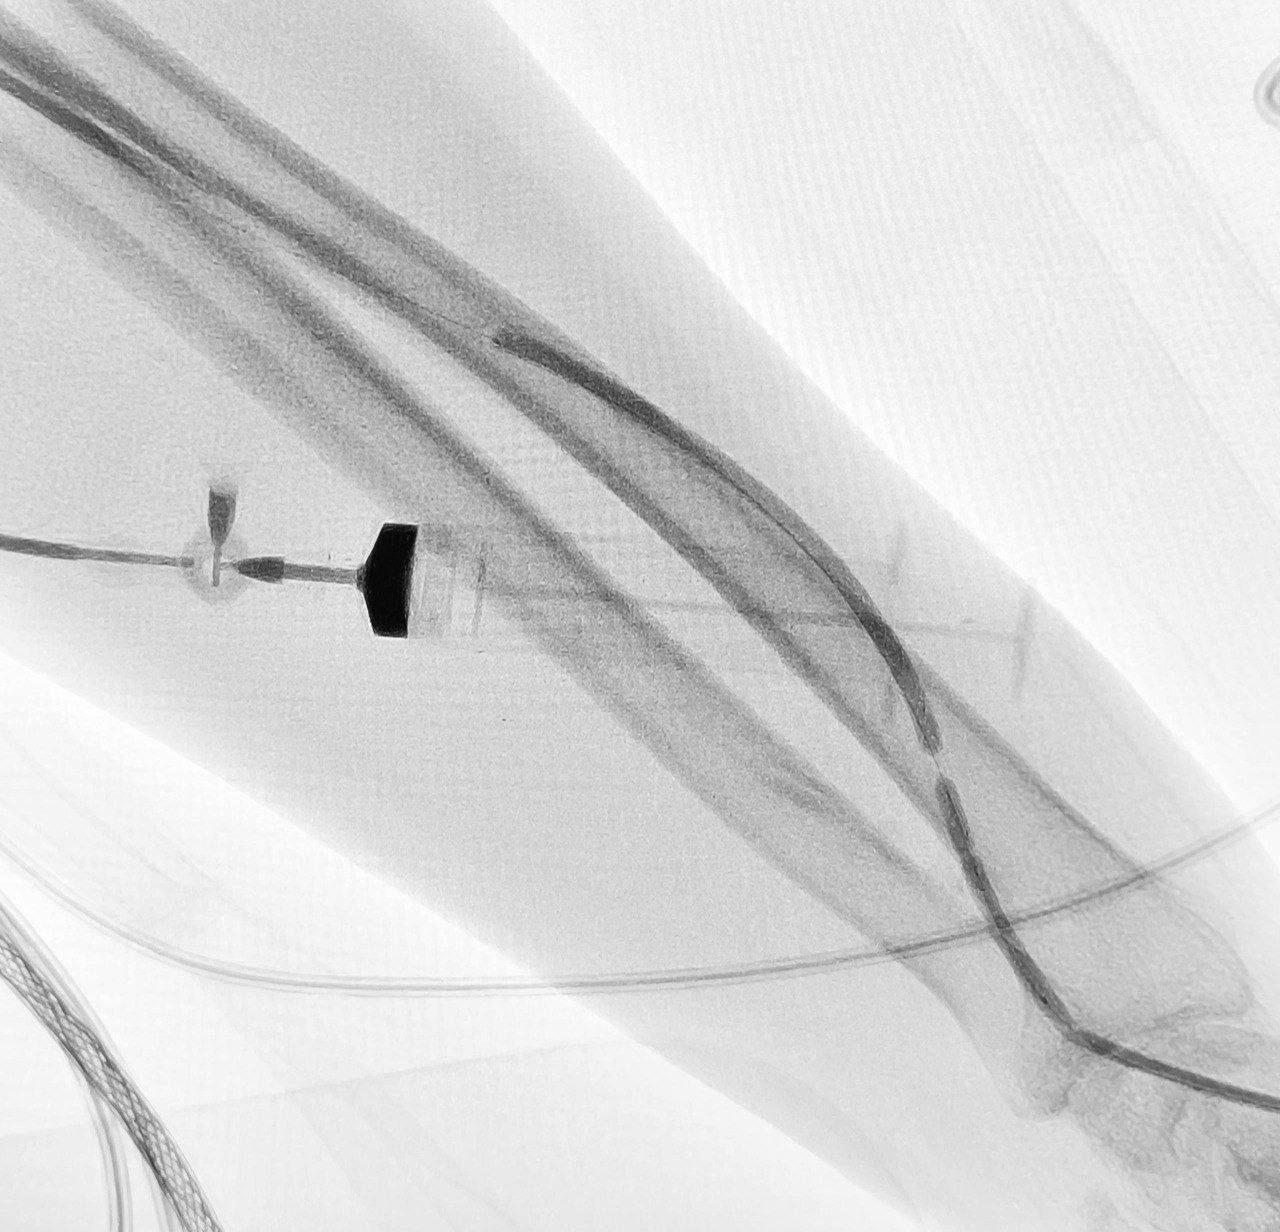

Врачи пошли по щадящему пути: через небольшой прокол под местной анестезией они провели катетер, устранили закупорку и расширили сосуд с помощью баллона. Всё — под рентген-контролем и без большой операции.

Главное — диализ можно было возобновить сразу, без недель ожидания. Быстро, точно и максимально бережно для пациента.